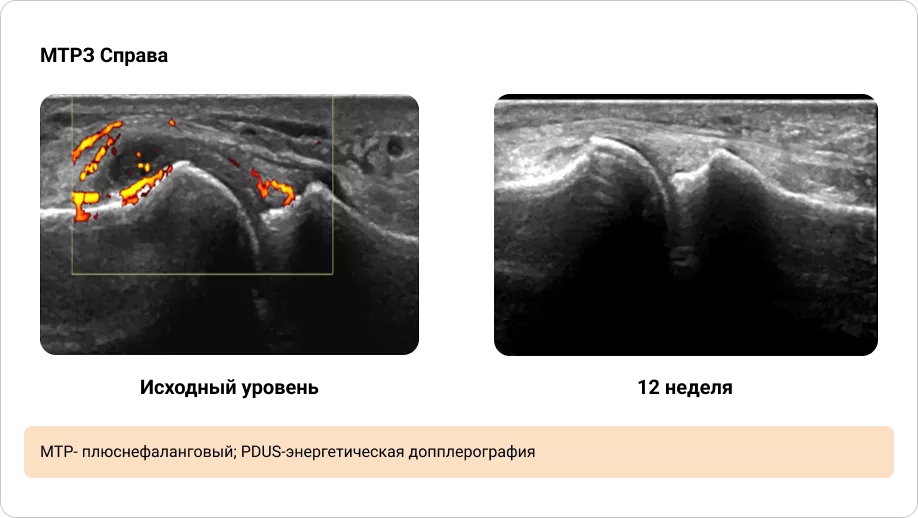

Приложение 4. Иллюстрация динамики синовита, выявленного при PDUS исходно и через 12 недель терапии (1/2)

Image

Иллюстрация динамики синовита, выявленного при PDUS исходно и через 12 недель терапии (1/2)

Приложение 5. Иллюстрация динамики синовита, выявленного при PDUS исходно и через 12 недель терапии (2/2)